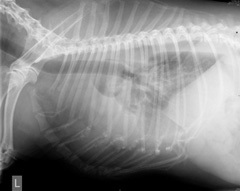

Body region between the neck and abdomen

The Thorax